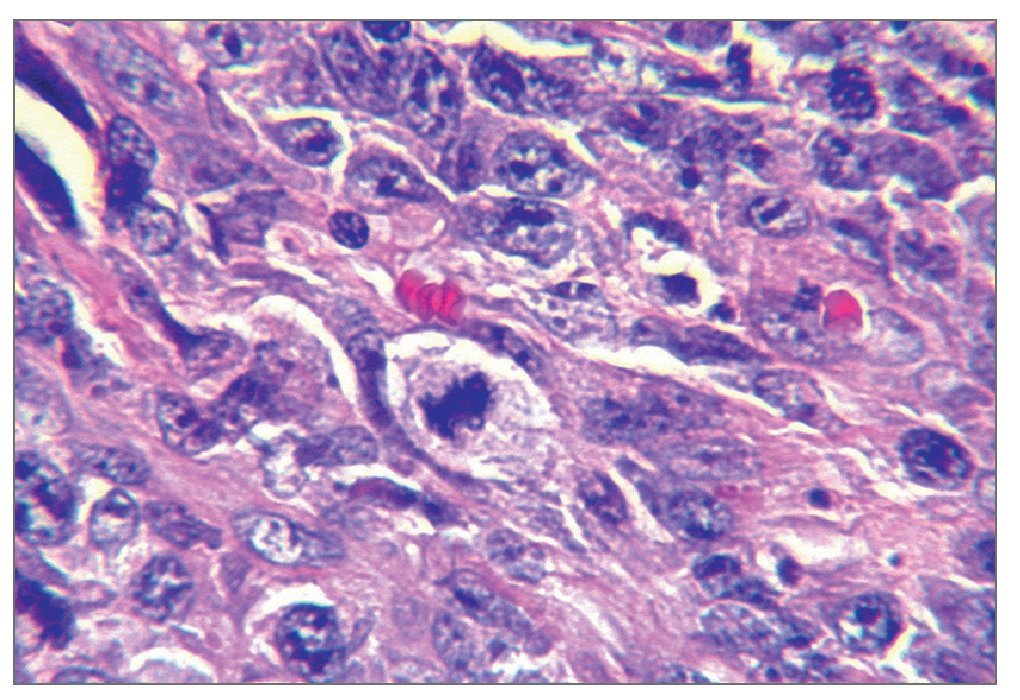

El examen histológico mostró un fuerte infiltrado difuso constituido por células blásticas linfoides grandes que presentaban núcleos ovoides y nucleolos prominentes, con presencia de numerosas mitosis atípicas (figs. 2a y 2b). La inmunohistoquímica mostró células pleomórficas positivas para CD20 y negativas para CD30, CD3, y anticuerpos Alk, confirmando el diagnóstico de LNH difuso de células B grandes (figs. 2c a 2f). Una vez completado el estudio se descartó linfoma sistémico.

Figura 2b. Campo que muestra mitosis atípicas (hematoxilina-eosina; 40 aumentos originales).